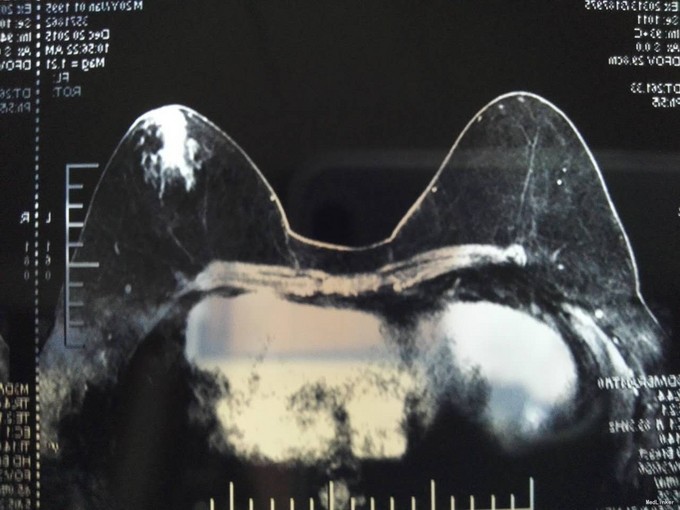

双乳基本对称,乳房呈“女性化”发育,乳头在同一水平线上。阴茎短小,未发育,无体毛。行MRI示:双乳腺体异常发育。性激素提示:睾酮 0.19ng/ml(正常成年男性 1.75-7.81ng/ml)。

入院后完善术前相关检查,无明显手术禁忌症,全麻下行“双乳腺体大部分切除术”,术后病理:双乳符合男性乳腺发育。